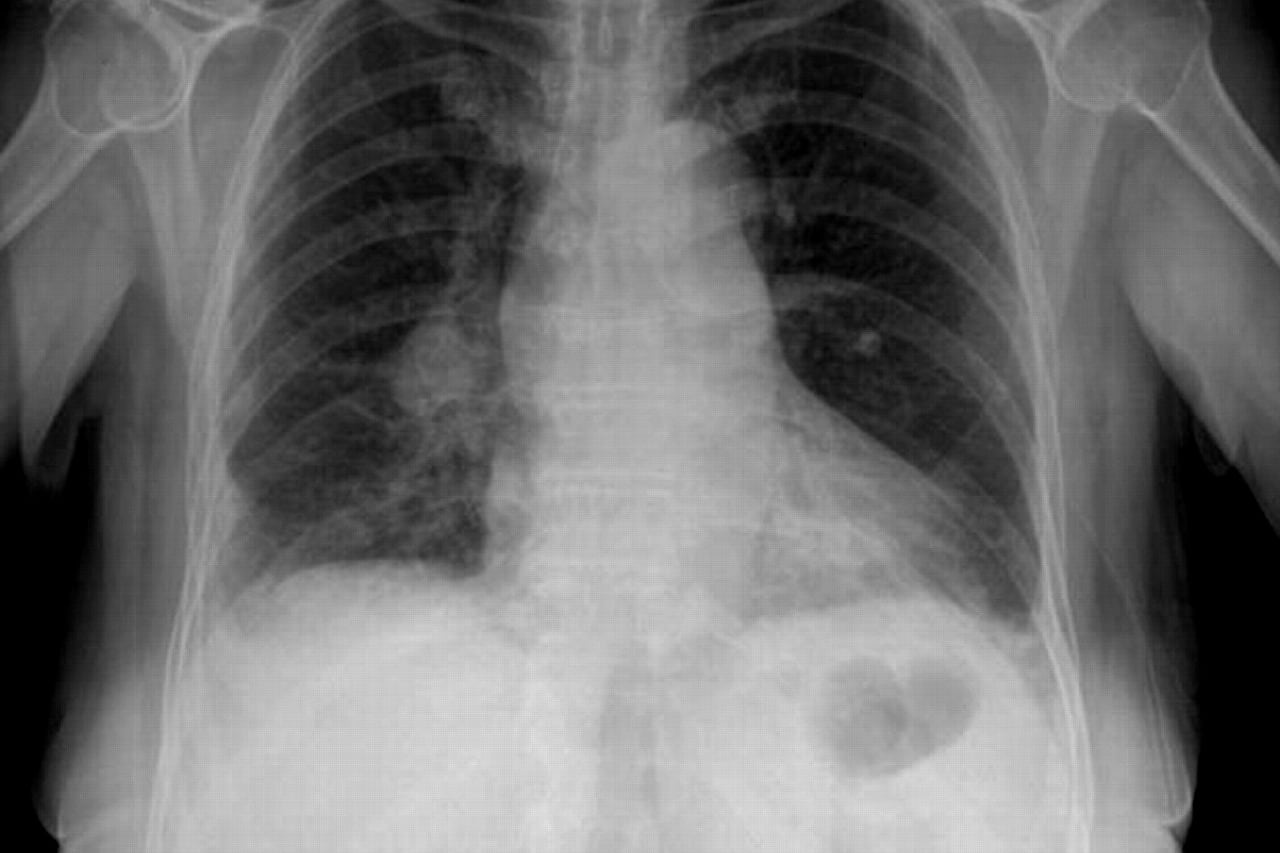

Una de las complicaciones que se pueden presentar en los pacientes con coronavirus es la neumonía bilateral, una afección al sistema respiratorio que ataca a los dos pulmones y, en los casos graves, puede precisar internación y causar la muerte.

La neumonía bilateral se desarrolla cuando los patógenos (ya sean virus, bacterias u otros microorganismos) inflaman los pulmones, formados por alvéolos que se llenan de aire al respirar.

Los alvéolos de los pacientes con neumonía están llenos de pus y líquido, lo que hace dolorosa la respiración y limita la absorción de oxígeno. Otros síntomas asociados a esta enfermedad son la fiebre intensa, dolor en el pecho, tos con pus, escalofríos, dificultad para respirar, nauseas, vómitos y diarrea.